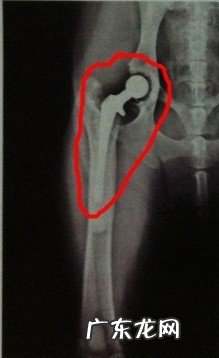

六岁田园犬的髋关 , 摆放稍有歪斜 , 基础在关节窝内二:全骨盆恢复术 , 指用一个假髋臼杯和股骨头部件更换衰退的髋关 , 常见于保守治疗失效的年青成犬 , 手术治疗通过率很高 , 但这与执行主治医生的工作经验有非常大关联 , 归属于比较繁杂的手术 , 必须有工作经验和训炼井然有序的医师来执行 。

文章插图

照片中高亮度且光洁的为人工合成髋关节 , 且髋臼也为光洁的人工合成杯